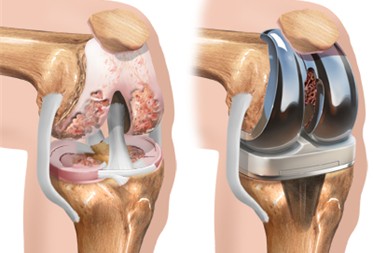

• Artroplastia unicompartimental

• Artroplastia total do joelho (prótese), em casos avançados